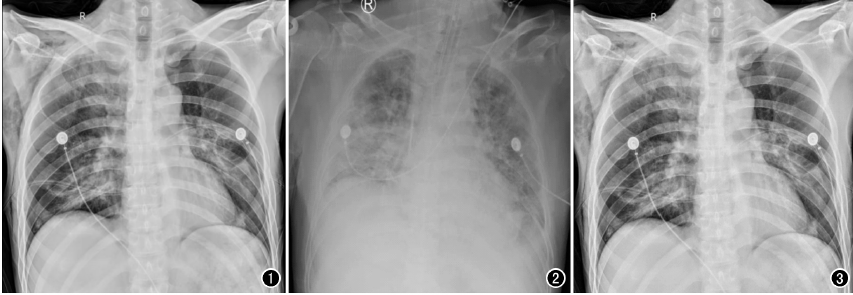

以心脏手术为例,开胸心脏手术多数是在低温、全麻和体外循环下进行,胸腔创伤较大、风险极高,心脏术后,心外科医师为了能及时了解术后患者的双肺复张情况、气管插管导管头端位置以及手术并发症等情况,需要及时对患者进行胸部X线片检查,以便观察气管插管位置,一般来说,插管位置下端应位于第3胸椎水平,过深或者过浅都将影响呼吸机的辅助效果,应确保位置准确,以免影响通气状况。另外,包括对于相关手术并发症的检查,包括:胸腔积液、气胸、肺不张等常见问题,需要及时进行胸部X光检查。相较于几百万像素的移动DR,百微移动DR,在图像质量上显示更清晰,检查效率更高,更利于医生及时进行处置。